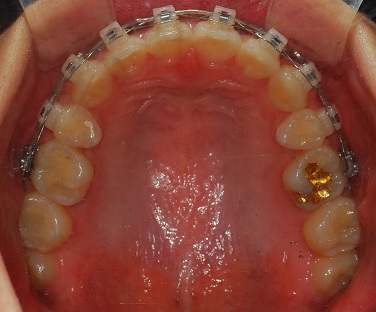

상악사진